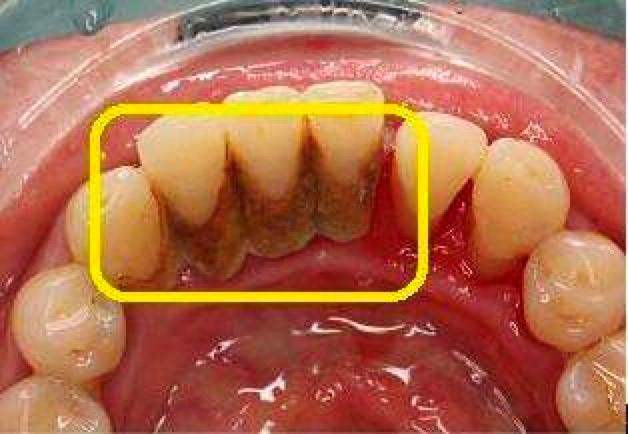

牙菌斑就像是由不同细菌组成的"细菌社区",它们依附在牙齿表面、牙缝间等部位,并且难以被水冲去或者漱掉,只能通过专门的洗牙器械清除。

别看牙菌斑肉眼看不见,但危害可不小。当它分解唾液中的糖,分解产生酸时,就会蛀牙;当它堆积在牙齿上,慢慢会钙化出牙结石。

什么是牙结石?打个简单的比方。假如牙齿是一棵树,牙周是培育牙齿的土壤,而牙结石就是占据良好土壤的石头。一旦牙结石形成,就会压迫牙龈,造成牙龈萎缩、肿胀甚至发炎的情况。

可见,牙菌斑和牙结石这类口腔杀手,不容忽视!